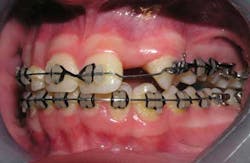

The following case study shows a Caucasian male, age 15 at the beginning of treatment. He had a peg lateral incisor No. 7 and was congenitally missing tooth No. 10. The treatment plan consisted of positioning tooth No. 7 for a veneer and opening space for an implant to replace tooth No. 10. After 30 months of orthodontic treatment had elapsed, there was still insufficient room for implant placement. There was sufficient room for the crown of No. 10, but the roots of teeth Nos. 9 and 11 were still too convergent to allow implant placement. The patient was leaving for college soon and was anxious to have treatment completed. The decision was made to have a periodontist do a corticotomy surgery to accelerate the tooth movement.

Corticotomy surgery was done and distal root movement was initiated on tooth No. 11 using a lever arm and elastic power chain. Root divergence was accomplished in eight weeks, and implant placement was accomplished at that time. The occlusion was detailed and orthodontic appliances were removed a short time later.